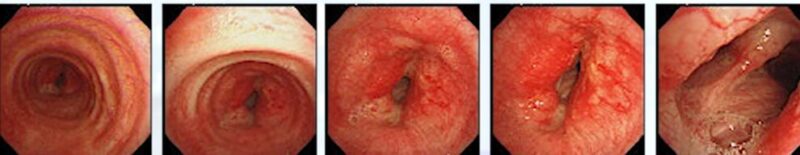

□気管支鏡検査

気道狭窄が確認できます。生検施行し、肺癌(LCNEC)の確定診断です。